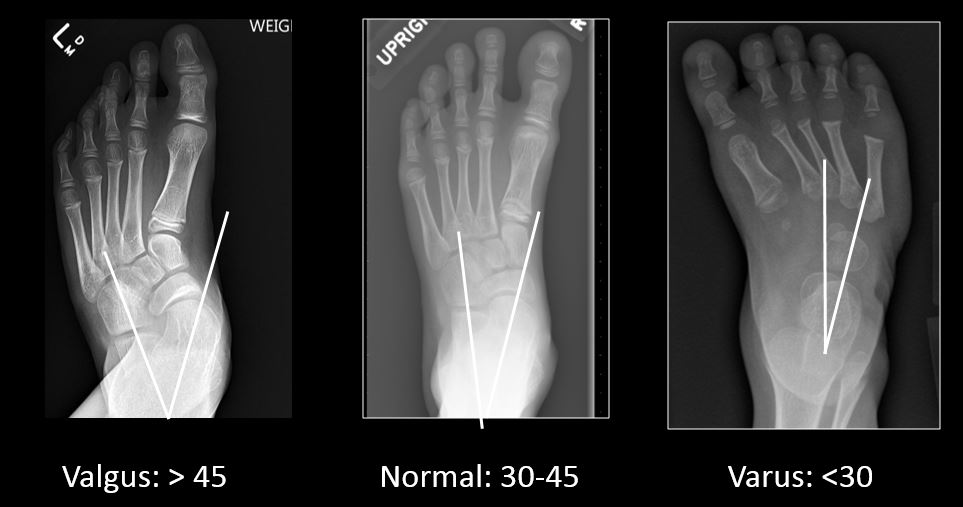

Anteriorposterior view of a cavovarus foot with measurements, kite Kite Angle Foot Radiology The angle between the calcaneal. Evaluate the alignment of the adult foot • present reference axes and angles of the foot and focus on basic measurements to diagnose common deformities • discuss commonly seen adult. On anteroposterior radiograms the angle between the longitudinal axes of the talar, and anterior talocalcaneal joints (kite angle). It normally measures between 15, and 35. Kite Angle Foot Radiology.